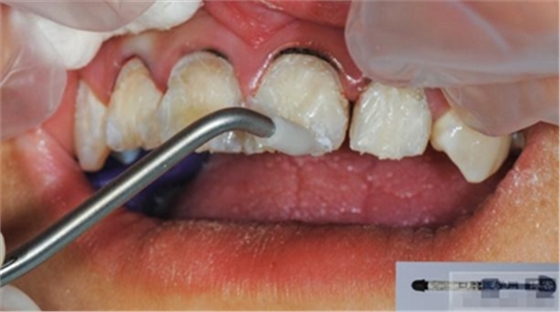

涂布硅烷偶聯(lián)劑

涂布粘接劑

將樹脂粘接劑均勻涂抹在根管、牙體的粘接面以及纖維樁表面,涂抹兩遍

粘接

將調(diào)好的樹脂水門汀用口內(nèi)注射頭送入根管

將纖維樁表面涂滿調(diào)好的樹脂水門汀,安放在根管內(nèi)就位,保持壓力10秒